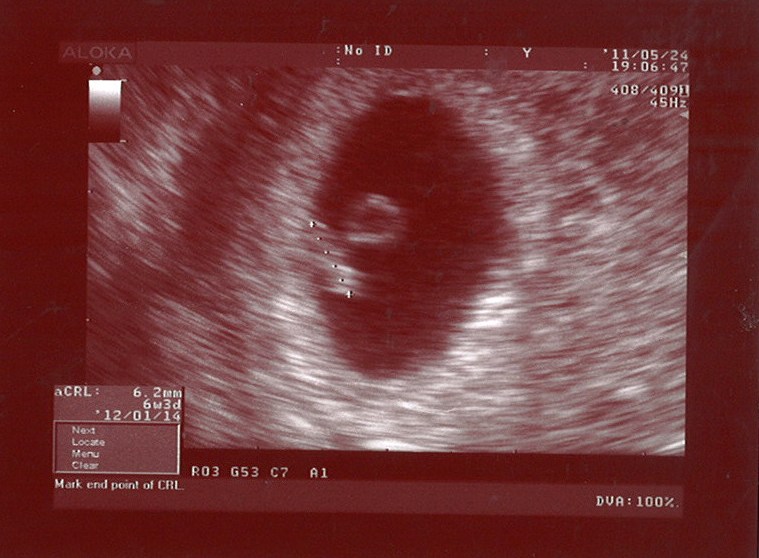

Foro 6 Semanas De Embarazo Y Test Negativo, EMBARAZADA CON PRUEBA NEGATIVA ¿ES POSIBLE, 15.72 MB, 11:27, 276,392, Osiris fonseca, 2019-08-30T02:38:00.000000Z, 3, Ecografia 2D & 4D Embarazo de 6 semanas Clinica Ginecologica Dr. Rafael, www.youtube.com, 1280 x 720, jpeg, WebSi después de confirmarse el embarazo con un test o prueba en sangre positiva, la hormona beta-hCG empieza a disminuir o directamente la prueba de. Web¿Puedo estar de 6 semanas de embarazo y test negativo? Si con anterioridad ya habías tenido un test de embarazo positivo y ahora te da negativa la prueba de embarazo., 20, foro-6-semanas-de-embarazo-y-test-negativo, Novedades y Muebles WebSi después de confirmarse el embarazo con un test o prueba en sangre positiva, la hormona beta-hCG empieza a disminuir o directamente la prueba de. Web¿Puedo estar de 6 semanas de embarazo y test negativo? Si con anterioridad ya habías tenido un test de embarazo positivo y ahora te da negativa la prueba de embarazo.